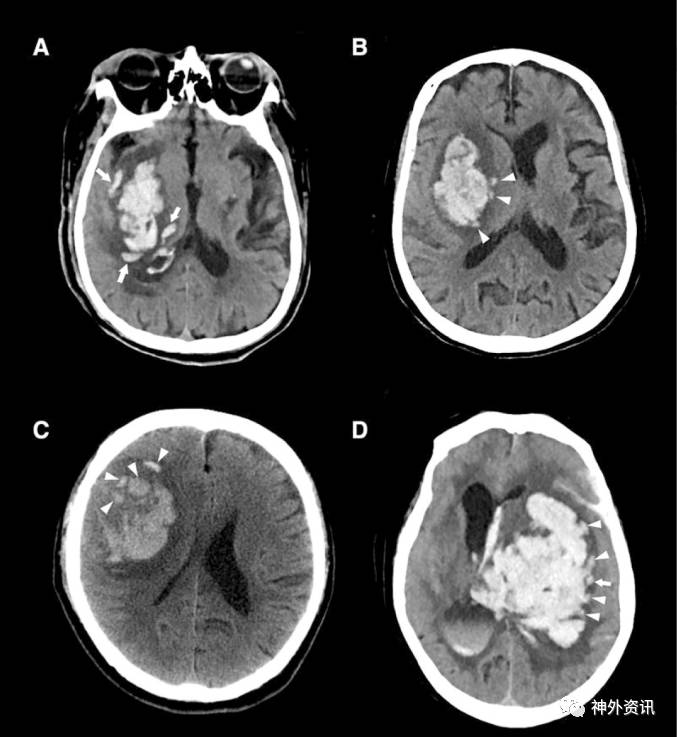

作者纳入2011年7月至2016年9月间收治的252例ICH患者。纳入标准:①年龄>18岁;②发病6小时内首次CT平扫;③首次CT后30小时内复查CT。排除标准:①在CT复查前行手术治疗的患者;②出血继发于脑动静脉畸形、外伤、颅内动脉瘤、脑肿瘤以及脑梗死性出血等;③凝血功能障碍相关性脑出血。CT平扫“岛征”定义为:≥3处散在的、均与主要血肿分离的小血肿;或≥4处小血肿,其中几个可以与主要血肿相连(图1、2)。血肿体积增加大于基础血肿量的33%或>6ml则定义为血肿扩大。患者第90天进行mRS评分,mRS评分≥3分为预后不良。通过多因素logistic回归分析CT平扫“岛征”与患者早期血肿扩大和预后的关系。

图2. 易误诊为CT平扫“岛征”的表现。A.1例真正的CT平扫“岛征”,3处散在、与主要血肿分离的小血肿,其主要血肿由4个分叶状组成;B.1例不规则形状的壳核出血,呈分叶状,但这种分叶不能视为“岛征”,箭头所指的微小的脑出血不是分离的血肿;C.1例壳核出血,箭头所指为2处散在小血肿,三角形所指是不规则的血肿边缘,不是“岛征”;D.1例基底节区脑出血,有2处分叶,但都属于主要血肿,故不能视为“岛征”。